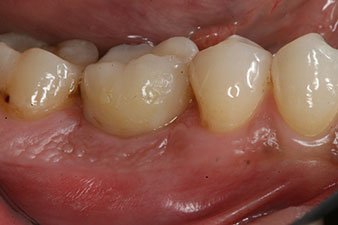

Fig. 8: The impression for the final crown is taken.

Therefore, successful osseointegration and adequate biological stability could be recorded, which enabled an impression to be taken in the same session.

The final pictures show the screw-retained monolithic composite crown in place and the x-ray check (Fig. 9 and 10) (6).

Fig. 9: The final composite crown was cemented on a PEEK hybrid abutment in the laboratory and can be screwed in place immediately.

Fig. 10: The x-ray check shows the success of the osseointegration and the crown screwed in position without a gap.